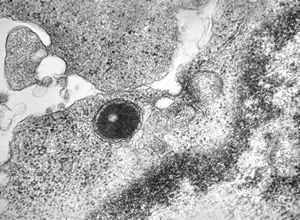

F,72y. | blood - lymphoplasmocellular leukemia

F,61y. | blood - lymphoplasmocellular leukemia